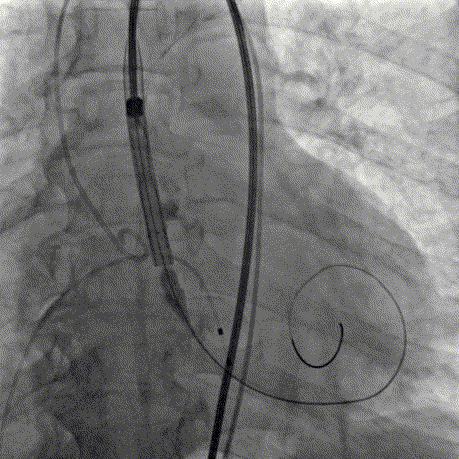

AV26瓣膜定位

AV26瓣膜工作位造影

AV26瓣膜释放

本例手术为重度钙化二叶式病变重度主动脉瓣狭窄TAVR手术,团块状钙化挤压存在移位瓣周漏风险,术前手术团队对患者进行了全面细致的评估,确定假体瓣膜锚定区域范围,制定术前释放策略。何柳平主任团队通力配合、精准释放,充分利用TaurusElite可回收功能,在瓣膜释放至2/3时,多角度评估瓣膜植入深度、锚定力以及冠脉灌注情况,确认瓣膜植入深度合适、锚定力稳定,缓慢逐个脱钩,进行瓣膜释放。释放后造影显示瓣膜膨胀良好,行血流动力学评估,跨瓣压差从术前100mmHg降至15mmHg,少量瓣周漏,手术圆满完成。